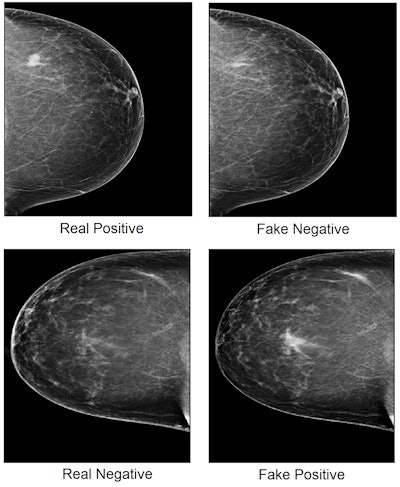

The team trained a deep-learning algorithm to distinguish cancerous and benign cases with more than 80% accuracy. The group also developed a GAN algorithm that inserted or removed cancerous regions from negative or positive images. The AI model then classified these adversarial images.

Zhou and colleagues found that the model was fooled by 69.1% of the fake breast images. Of the 44 positive images made to look negative by the adversarial network, 42 were classified as negative by the model. Of the 319 negative images made to look positive, 209 were classified as positive.